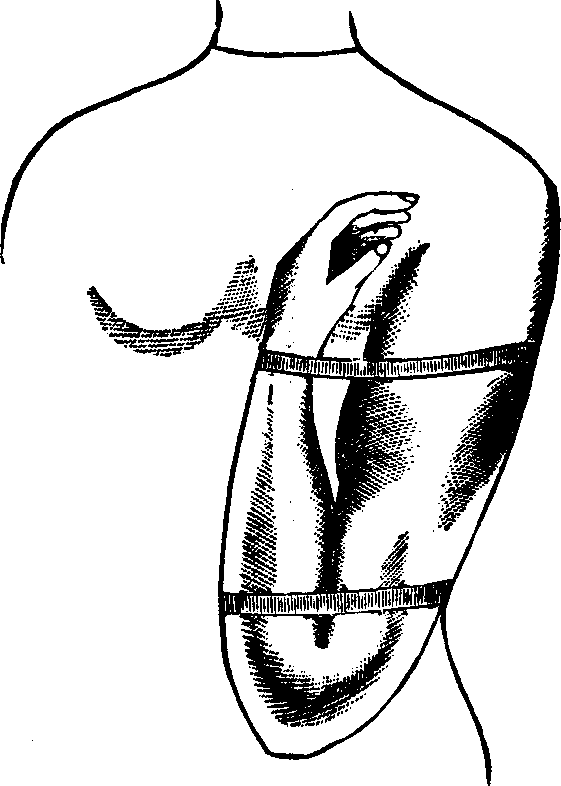

Fig.

24. A representation of the superficial layer of muscles on the anterior

portion of the body.

Fig.

25. A representation of the superficial layer of muscles on the posterior

portion of the body.